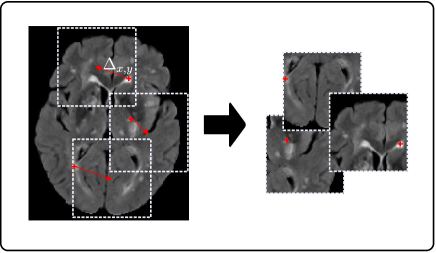

Generally, in the segmentation of pathologies, healthy tissue is present in far larger quantities than pathological. For example, in WMH segmentation the number of voxels labeled as WMH (regardless of the underlying pathology) is very small compared to those labeled background/healthy tissue, which leads to a significant class imbalance (similar-to\sim99.8% of the voxels in the dataset used in this work are labeled as background/healthy tissue in our training set). Hence, although dense training (where whole images or slices are used) is a staple in computer vision with natural images [47], it is less intuitive for WMH segmentation. Therefore, patch sampling is used in this work in order to alleviate the class imbalance problem. There are several techniques that could be used to sample patches for training. For example half of the samples could be extracted from locations centered on healthy tissue and half centered on WMH tissue [39], however this strategy does little for the class imbalance when large patches are being considered, as individual patches tend to still be highly class imbalanced at a voxel level. Another option, is to sample patches centered at WMH locations only, which in fact reduces the healthy tissue class to similar-to\sim90%. However, both strategies, in combination with the proposed architecture that has a field of view comparable to sample size, would lead to a location bias, where WMHs are always expected in the center of the patch. Instead, we propose that after defining a random subset of WMH voxels from which to extract training patches, a random shift Δx,ysubscriptΔ𝑥𝑦\Delta_{x,y} of up to half the patch size be applied in the axial plane before patch extraction to augment the dataset. Figure 2 details this procedure. It is important to point out that the location sensitivity mentioned here, is generally not an issue with dense training in natural images, where different classes can either appear anywhere in a scene (e.g. a face might be located anywhere), or class location gives a meaningful description (e.g. sky tends to be in the upper part of a scene). This problem only occurs when sampling patches from training images in a systematic way, such as proposed here.

Refer to caption

Figure 2: Training patch sampling.